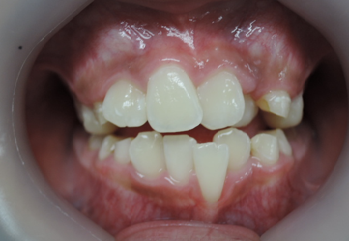

今回の症例は、悪い歯並びの代表例である八重歯です。

歯並びが悪いだけでなく、困ったことに犬歯から奥歯にかけて歯が嚙み合っていない開咬の状態です。